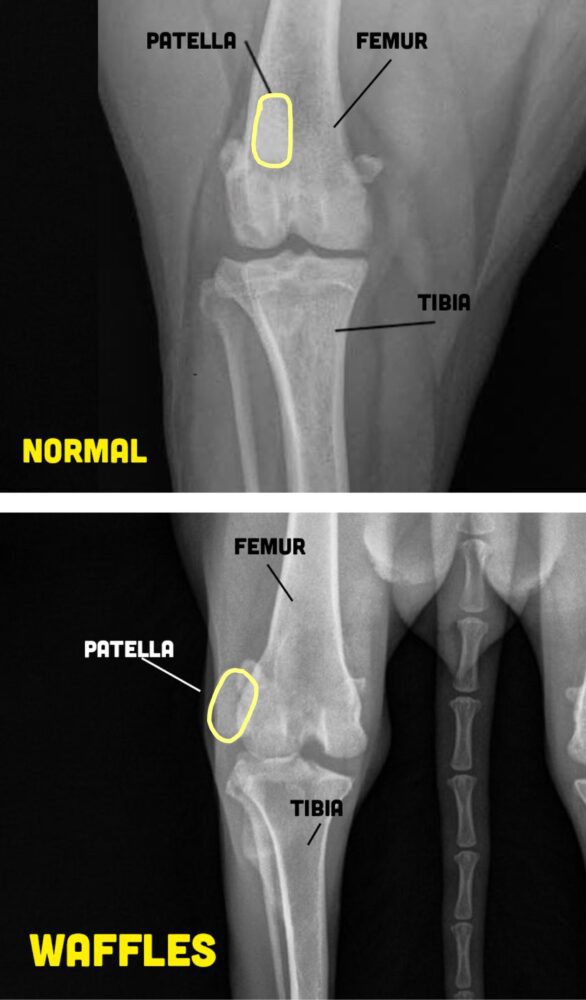

Waffles landed at Arizona Humane Society after being found as a stray. It was very clear that she had mobility issues with her hind limbs, and needed medical attention. AHS learned that Waffles had severe patellar luxations that caused a painful, hunched walk and visible difficulty getting around. After deciding that Waffles’ condition was too severe for them to perform surgery, she was placed on the E-list. Waffles urgently needed rescue and medical care, and we are so grateful to have found a foster who stepped up for this petite 3 year old girl, giving her the chance she deserved.

• E-listed at AHS for severe patellar luxations

• Had the most sad, hunched walk that needed surgery